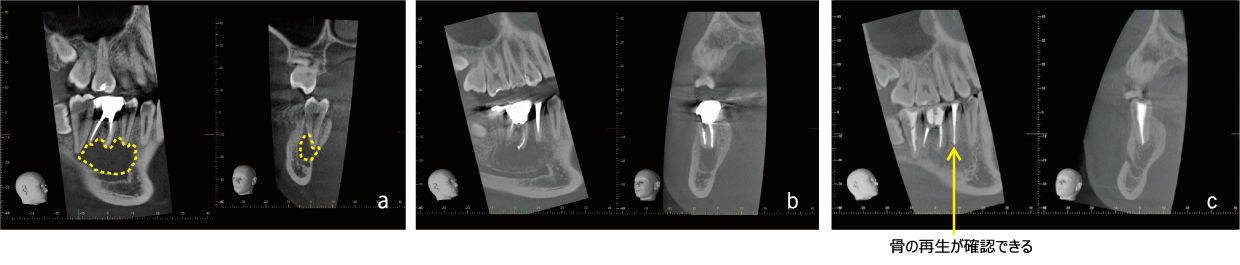

EMAT is a regenerative treatment that revives the "alveolar bone" that supports teeth by activating bone-forming cells called "osteoblasts," which are naturally present in the patient. At the same time, it has the effect of sterilizing bacteria that inhibit the preservation of teeth, so it can be expected to improve the symptoms you are suffering from.